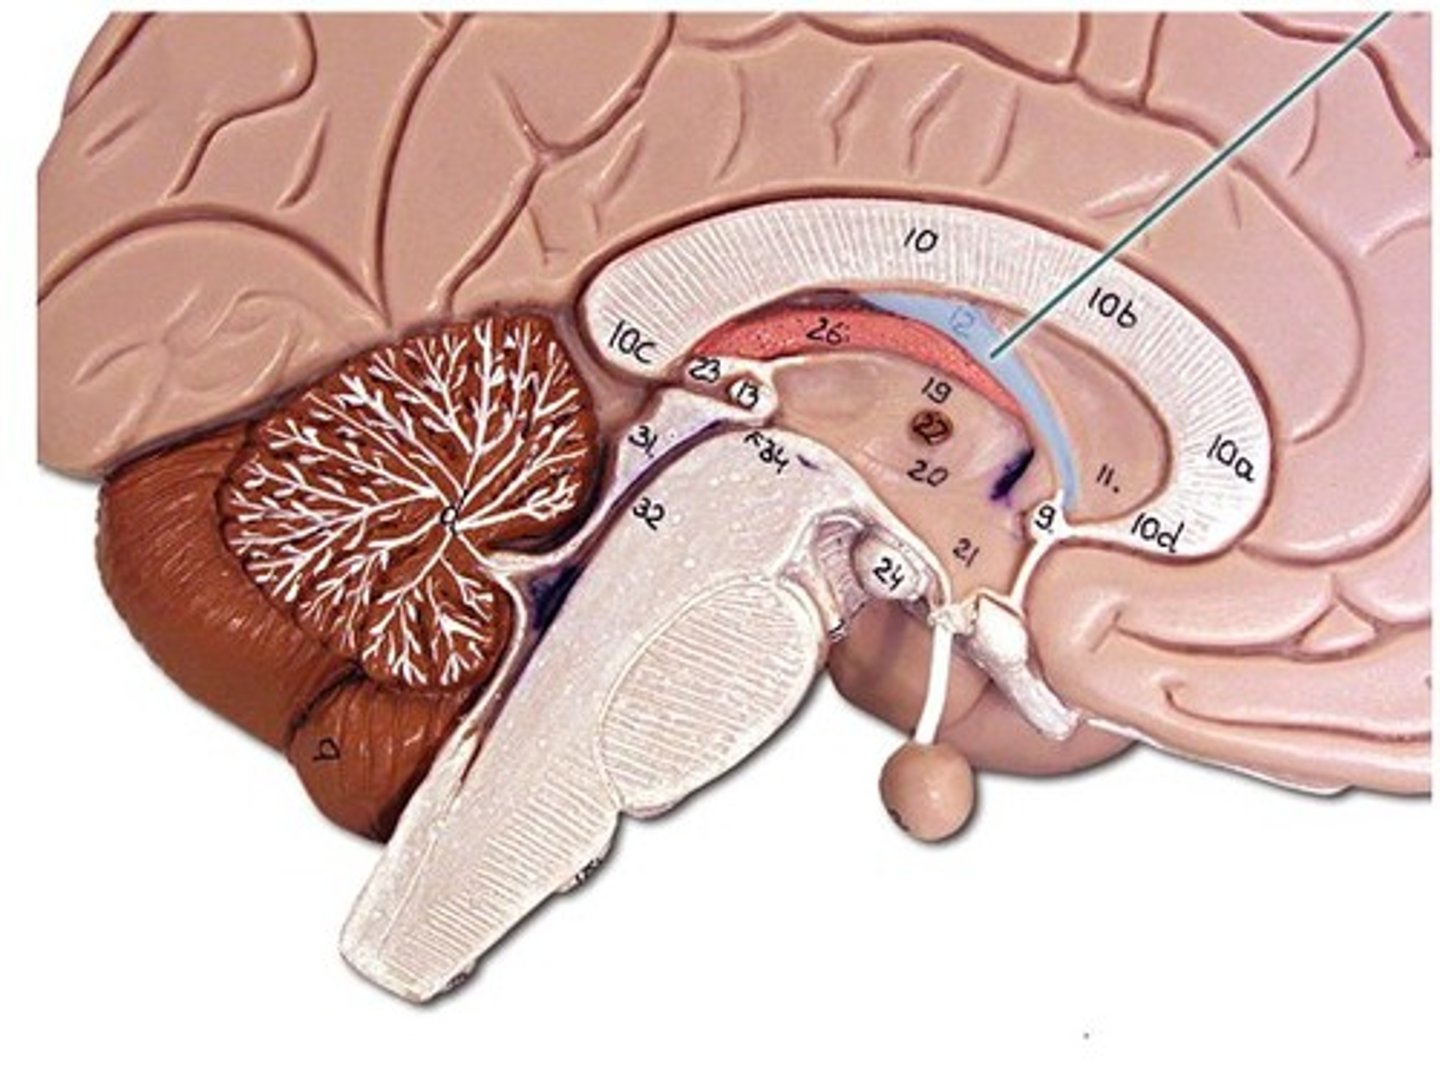

Dura mater

outermost layer of meninges - 2 layers, periosteal and meningeal

What is contained between the inner and outer layers of dura?

venous sinuses

what are the venous sinuses? where do they drain?

cerebrospinal fluid, they drain out of the internal jugular

superior sagittal sinus

inferior sagittal sinus

what are dural folds?

folded layers of dura where there is no sinus

falx cerebri

separates the two cerebral hemispheres

tentorium cerebelli

separates cerebrum from cerebellum

falx cerebelli

separates the two hemispheres of the cerebellum

arachnoid mater

middle layer of meninges, weblike

what is in the subarachnoid space?

cerebrospinal fluid

pia mater

"delicate mother," innermost layer of meninges

what attaches the pia mater to the surface of the brain?

collagen fibers

lateral ventricles

third ventricle

fourth ventricle

interventricular foramen

connects lateral ventricles to third ventricle

cerebral aqueduct

connects the third and fourth ventricles

choroid plexus

on the floor of all the ventricles, produces CSF

arachnoid villi

reabsorb/drain CSF into venous blood

diencephalon

thalamus and hypothalamus

thalamus

relay station for all somatosensory information

intermediate mass

connection between the two thalami across the third ventricle, dumbbell shape

hypothalamus

brain region (many nuclei) in charge of maintaining homeostasis

pituitary gland

produces hormones

mammillary bodies

olfactory relay stations

epithalamus

region above midbrain that contains pineal gland

pineal gland

regulates sleep-wake cycles, secretes melatonin

cerebellum

balance, equilibrium, gross motor movement

vermis (cerebellum)

The tissue between the two cerebellar hemispheres

arbor vitae

"tree of life," white matter of cerebellum

corpus callosum

the large band of neural fibers connecting the two brain hemispheres and carrying messages between them

septum pellucidum

membrane that separates lateral ventricles

basal nuclei

internal masses of gray matter, smooth out motor movement

fornix

band under septum pellucidum